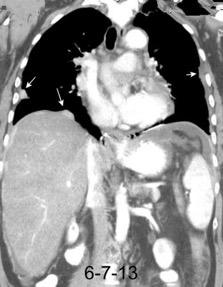

Empiema pleural secundario a carcinoma de la flexura esplénica (masa visible)

Lian R et al. Empyema caused by a colopleural fistula. Medicine (Baltimore) 2017/Osada T,, et al. Thoracic empyema associated with recurrent colon cancer: report of a case and review of the literature. Dis Colon Rectum 2001